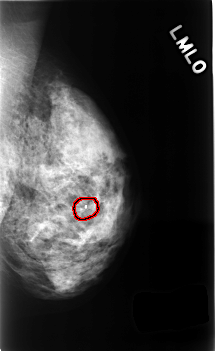

C_0498_1.LEFT_MLO

FILE: C_0498_1.LEFT_MLO.OVERLAY

TOTAL_ABNORMALITIES 1

ABNORMALITY 1

LESION_TYPE CALCIFICATION TYPE LUCENT_CENTERED DISTRIBUTION N/A

ASSESSMENT 2

SUBTLETY 5

PATHOLOGY BENIGN_WITHOUT_CALLBACK

TOTAL_OUTLINES 1

BOUNDARY